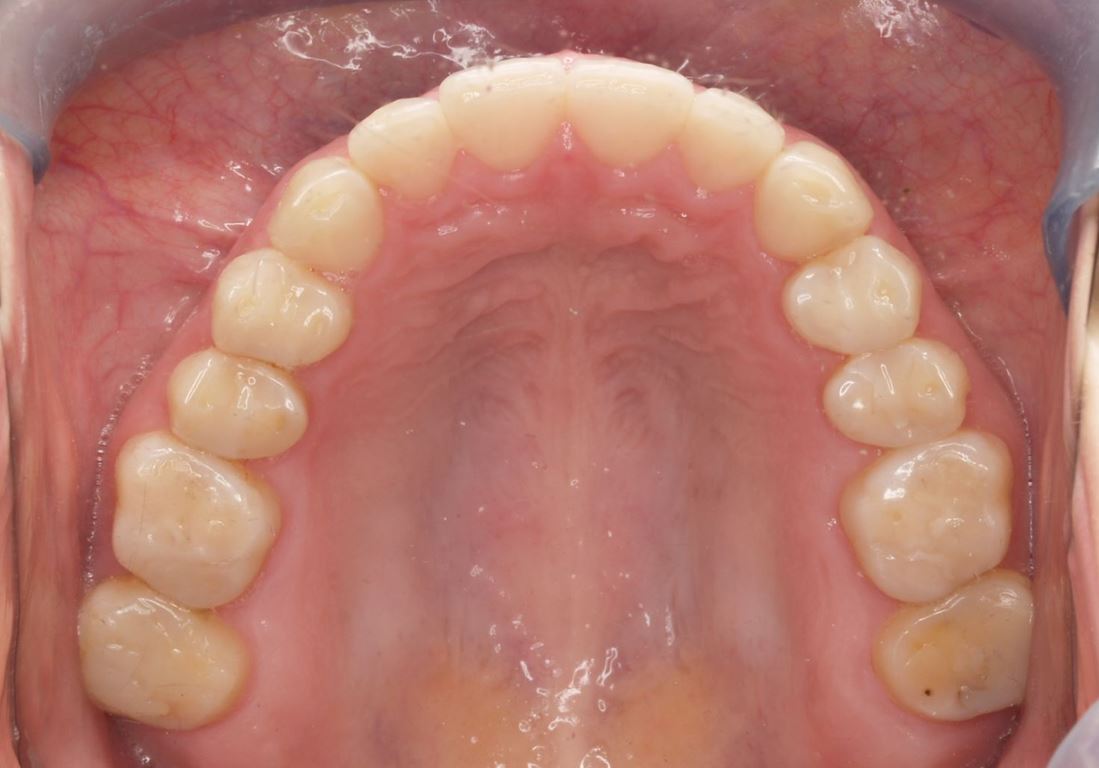

Ryciny 39-50 przedstawiają stan po zakończeniu leczenia.

Drugie zęby trzonowe nie zostały włączone w rekonstrukcję pomimo znacznej utraty wysokości koron. Dzięki temu podniesienie wysokości zwarcia mogło być zminimalizowane oraz uniknięto konieczności preparacji zniszczonych powierzchni zwarciowych tych zębów. Po przebudowie warunków zwarciowych na pozostałych zębach uzyskano prowadzenie przednie i kłowe, co potencjalnie dało ochronę zębów trzonowych przed destrukcyjnymi siłami bocznymi.